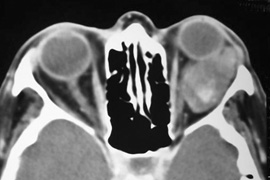

Magnetic resonance imaging is useful in selected cases, especially when evaluating the orbital cranial junction. Significant bony artifact and a lack of orbital fat in the orbital apex make CT scan resolution of the orbital apex structures poor. Because cortical bone has low signal on MRI, there is no bone artifact when viewing the orbital apex on MRI. The lack of intervening fat in the apex to provide contrast is overcome on MRI because contrast is provided by the individual nuclear characteristics of each tissue so that the orbital apex structures are visualized well. Consequently, conditions that affect the optic nerve and chiasm, such as optic nerve meningioma and glioma, generally are evaluated with MRI rather than CT scan (Fig. 2).

Fig. 2. A. Axial orbital CT scan of right optic nerve meningioma. Note lack of detail in orbital apex. B. Axial orbital MR image, same patient. Note increased detail in orbital apex owing to lack of bone artifact. C. MRI with gadolinium contrast. Note extension into brain not easily appreciated with CT scanning or MRI without contrast.